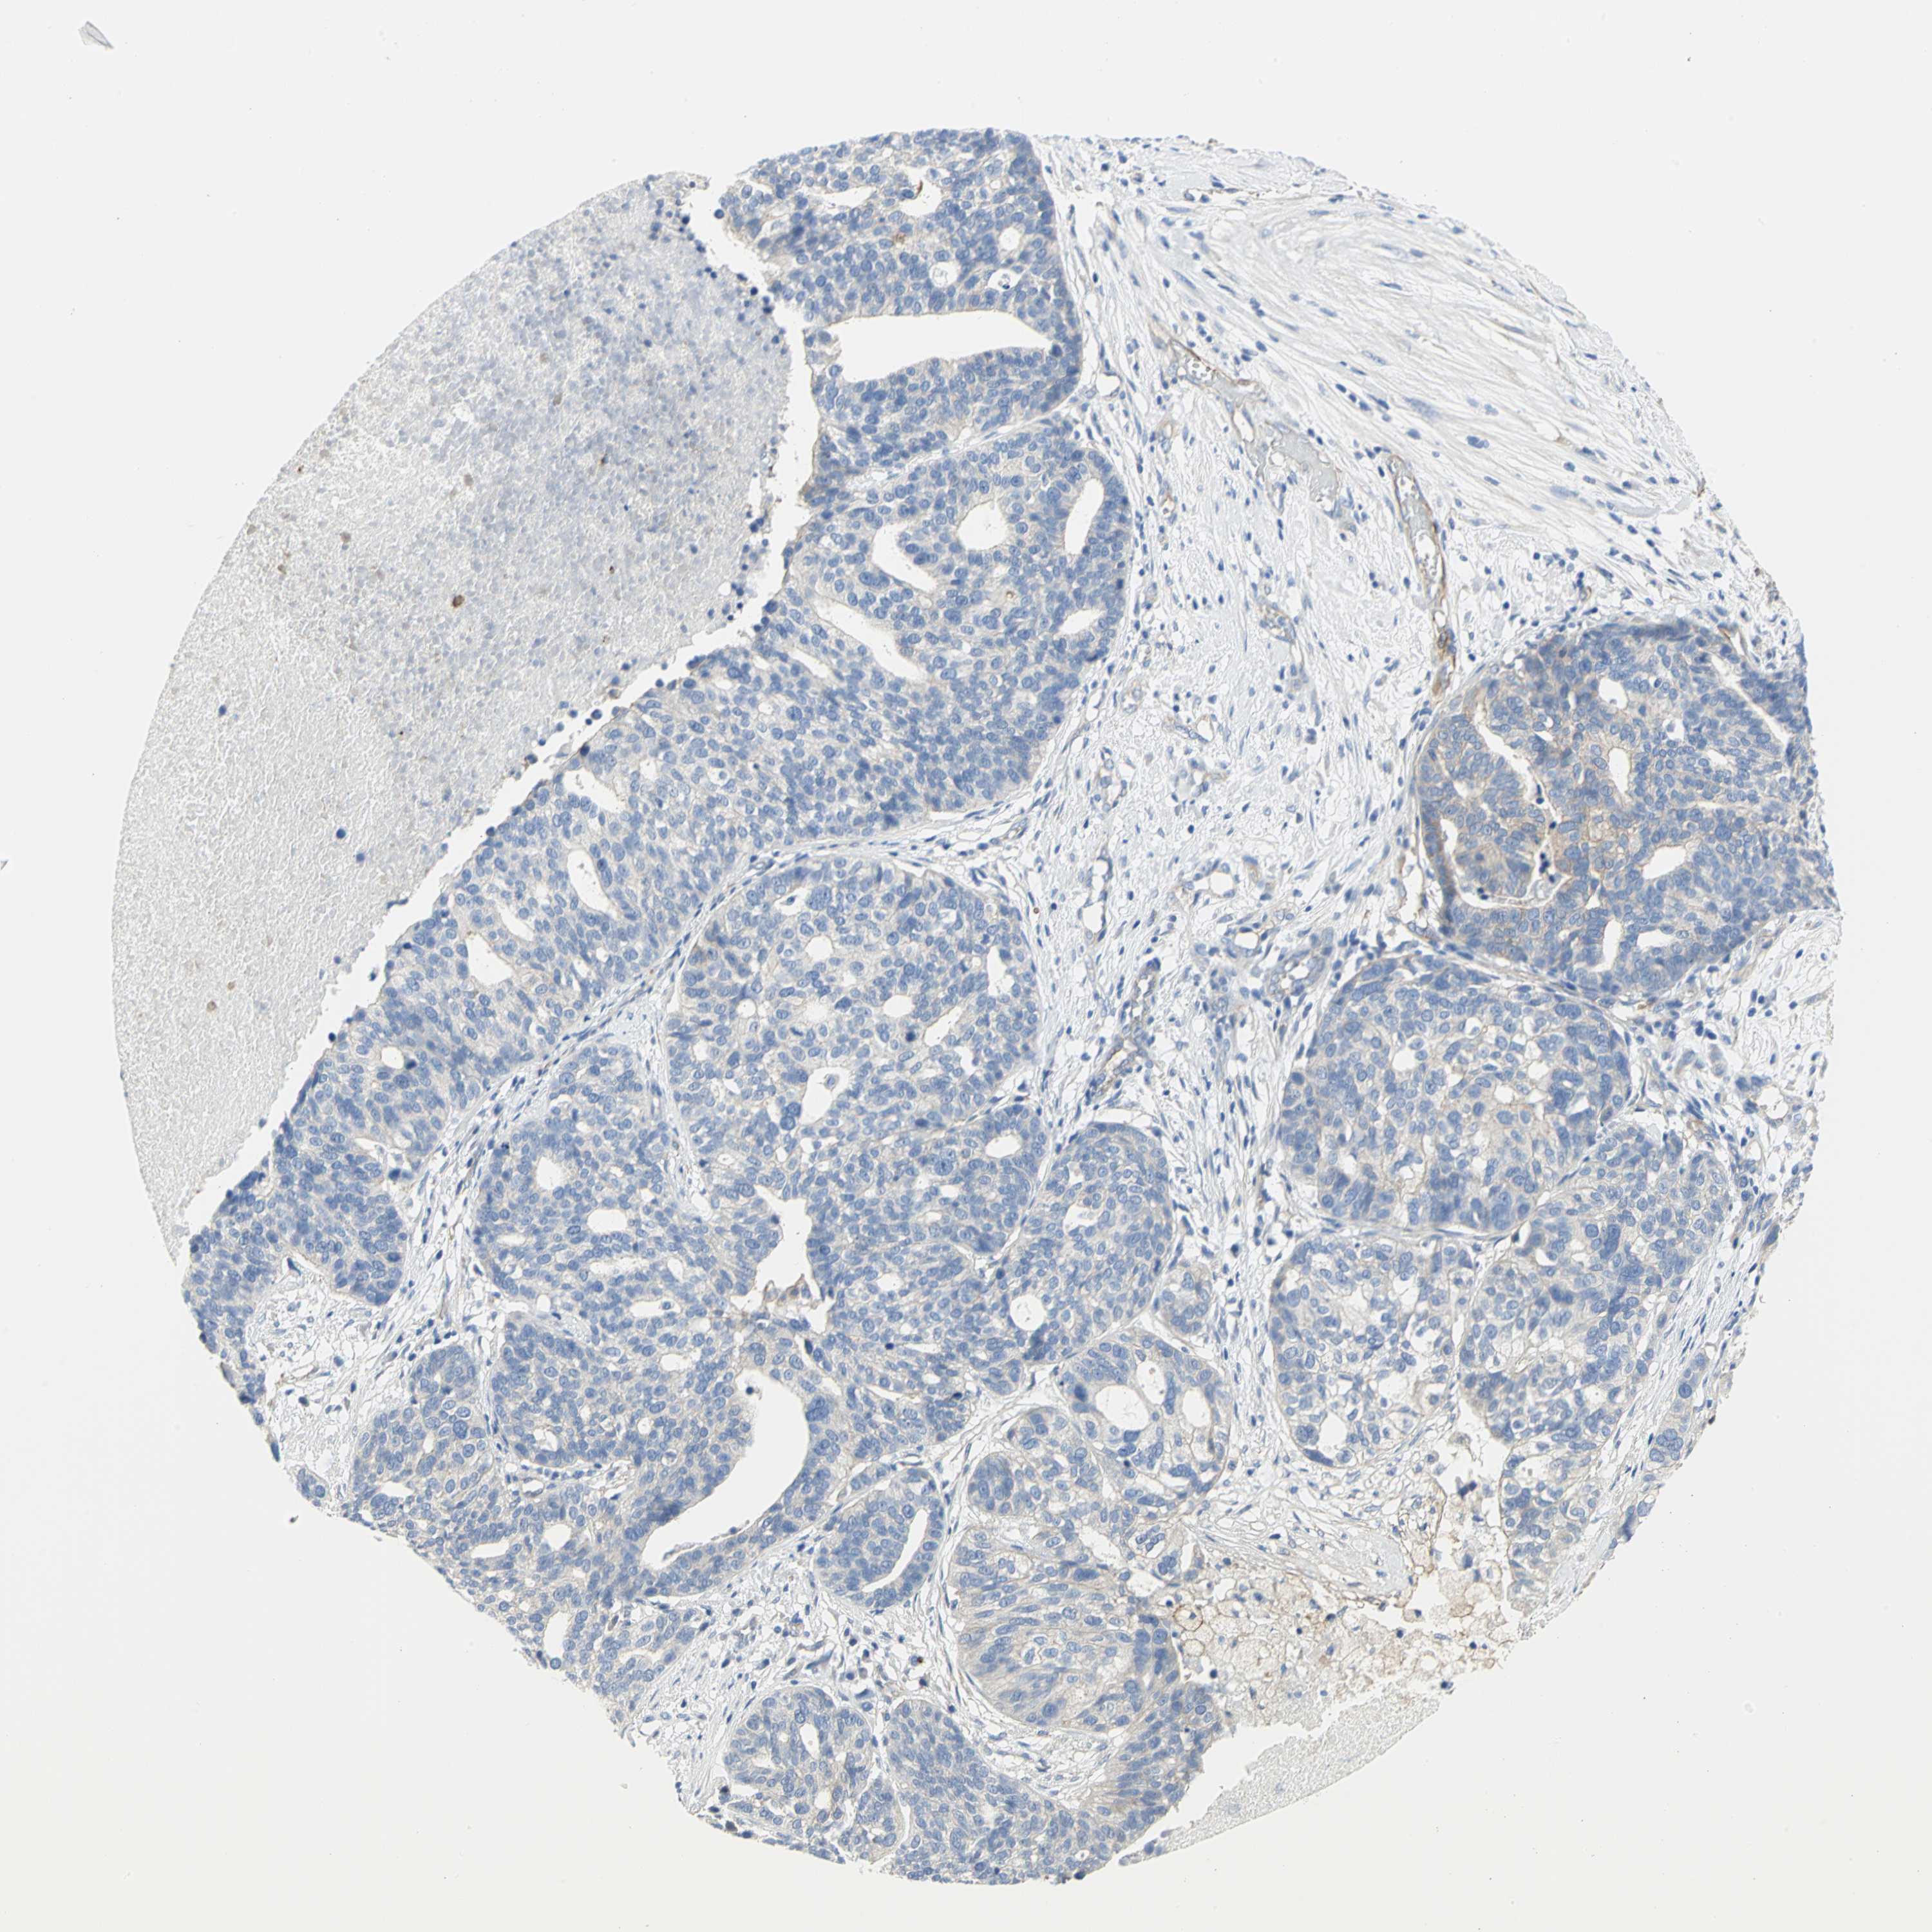

OVARIAN CANCER - Protein expressioni

A mouse-over function shows sample information and annotation data. Click on an image to view it in a full screen mode. Samples can be filtered based on level of antibody staining by selecting one or several of the following categories: high, medium, low and not detected. The assay and annotation is described here.

Note that samples used for immunohistochemistry by the Human Protein Atlas do not correspond to samples in the TCGA dataset.

Antibody stainingi

Antibody staining in the annotated cell types in the current human tissue is reported as not detected, low, medium, or high, based on conventional immunohistochemistry profiling in selected tissues. This score is based on the combination of the staining intensity and fraction of stained cells.

Each image is clickable and will lead to virtual microscopy that enables deeper exploration of all samples and also displays staining intensity scores, fraction scores and subcellular localization as well as patient and tissue information for each sample.

Antibody HPA004747

Antibody HPA004886

Antibody CAB019322

Cystadenocarcinoma, serous, NOS

Carcinoma, endometroid

Carcinoma, NOS

Cystadenocarcinoma, mucinous, NOS